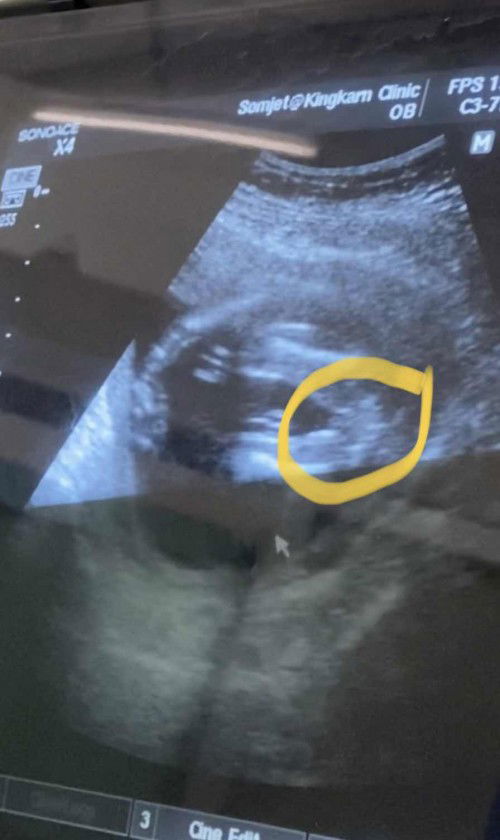

ญ หรือ ช จ้าาาาา

#18วีค #ท้องแรก

ช่วยดูหน่อยจ้าาาา

ในรูปแม่ๆว่า ช หรือ ญ